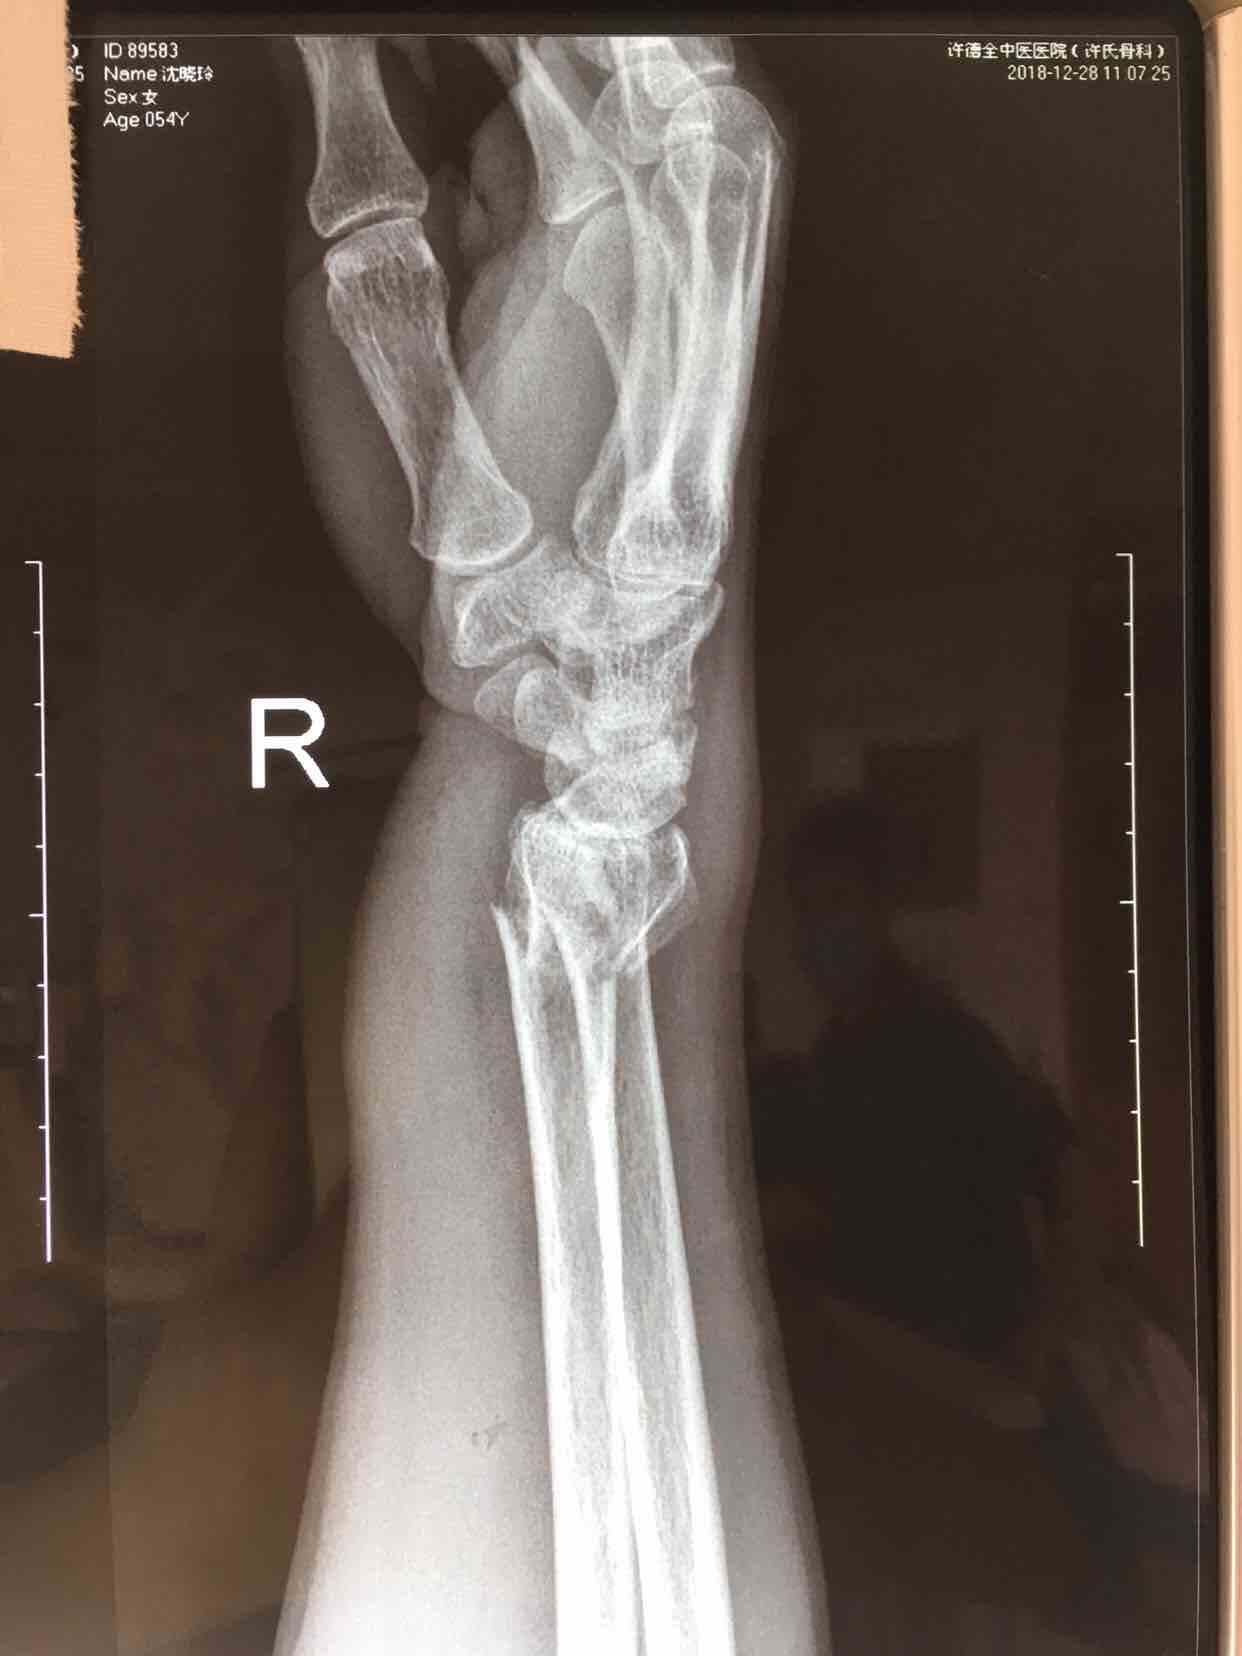

患者:女/五十八岁

摔伤后左手肿痛,活动受限1小时。

生命体征平稳,心肺复未见异常。左腕部肿胀明显,局部皮色皮温正常,畸形,压痛及纵向叩击痛阳性,腕关节活动受限,感觉血运正常。

诊断左colles骨折